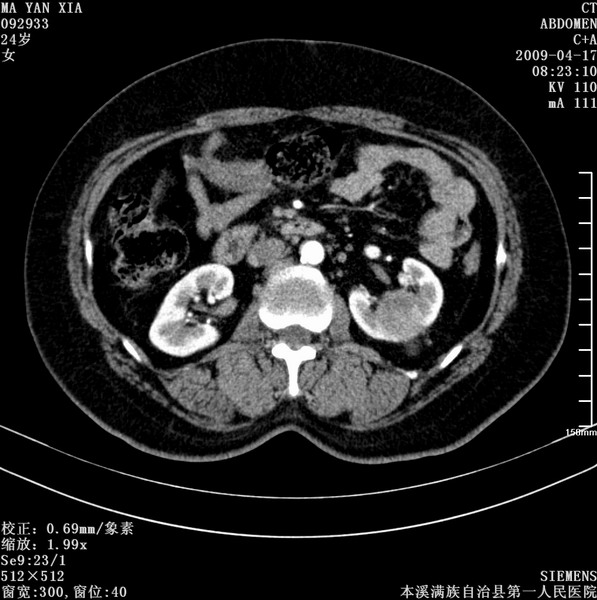

标题: CT19443:肾脏肿瘤两个区强化不一样。 [打印本页]

标题: CT19443:肾脏肿瘤两个区强化不一样。

女,51岁,体检时发现肾脏占位,建议ct增强。无任何自觉症状。

典型的不均匀强化,左肾癌